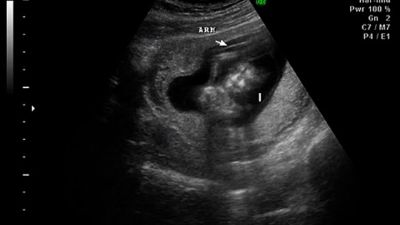

وقد ظهر جهاز حديث يسمى السونار للكشف عن عمر الحمل وحالة الجنين وجنسه، يستخدم جهاز السونار لإنشاء صورة ثنائية الأبعاد على شاشة الكمبيوتر، يستمر حوالى عشرين دقيقة، ويعطي معلومات عن عمر الحمل وتقييم الجنين، يقيس هذا الاختبار حركة تدفق الدم والسرعة التي ينتقل فيها الدم في الرحم أو الحبل السري أو في قلب الجنين أو حول جسمه، سنتعرف في هذا المقال عن الوقت الذي يمكننا فيه معرفة جنس الجنين، وهل يخطئ السونار في تحديد نوع الجنين في الأسبوع 12.

علامات تساعد على تحديد جنس الجنين بالسونار

الكثير من الأمهات الحوامل ينتابها الفضول لمعرفة جنس الجنين في وقت مبكر من الحمل، والكثيرات يطرحن العديد من الأسئلة منها، هل يخطئ السونار في تحديد نوع الجنين في الأسبوع 12، وكانت الإجابات متباينة في هذا الموضوع، لكن الغالبية العظمى من أطباء الحمل والتوليد أكدوا أن نسبة الخطأ مرتفعة، ويجب الانتظار إلى ما بعد الأسبوع الثامن عشر، يوجد بعض العلامات التي تساعد على تحديد جنس الجنين بالسونار، وهي على النحو الآتي:

1. لتحديد جنس الأنثى

هناك بعض العلامات تساعد في تحديد جنس المولود إذا كانت أنثى بواسطة السونار:

- علامة همبرغر: وتعني أن شكل أعضاء الأنثى التناسلية كشكل ساندويش همبرغر.

- التشريح السهمي: يمتاز كل جنس بتشريح سهمي مختلف عن غيره، حيث يتواجد قسم شبيهه بالنتوء في آخر العمود الفقري، ويكون متوجه نحو الأسفل عند الجنين الأنثى.

2. لتحديد جنس الذكر

هناك علامات تساعد في تمييز جنس المولود الذكر بواسطة السونار منها:

- التشريح السهمي: حيث يحدد جنس الجنين على أنه ذكرًا في حال كان النتوء في نهاية العمود الفقري متجهًا نحو الأعلى.

- جهة تدفق البول: ممكن أن يستطيع الطبيب أحيانًا أن يرى تدفق البول في الجنين، ويكون ذكرًا في حال كان التدفق متجهًا للأعلى.

- الأعضاء التناسلية الذكرية: يمكن للطبيب رؤية الأعضاء التناسلية الذكرية في فترة الحمل الممتدة بين الأسبوع 18-20 ، وهذا ما يجعل تحديد جنس الجنين أسهل.